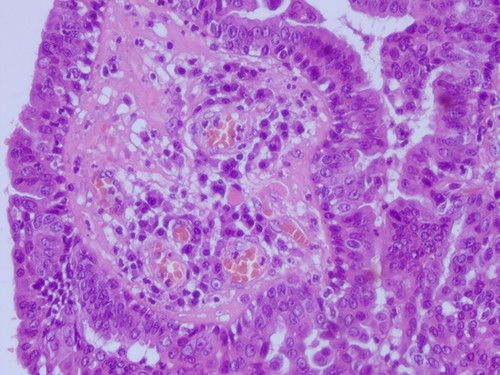

The histopathological examination found cystic invaginations of the infundibular epithelium projecting into the dermis, covered by a double cell layer (Fig. 2), proliferation of glands with prominent papillary architecture (Fig. 3) and fibrous cores containing numerous stromal plasma cells (Fig. 4). Other findings include verrucous (papillomatous) epidermal hyperplasia with hyperkeratosis and hypergranulosis (Fig. 5), irregular duct-like structures and cystic spaces (Fig. 6) and glands with double layer of cuboidal columnar epithelium and numerous stromal plasma cells (Fig. 7). These findings are compatible with Syringocystadenoma papilliferum with no signs of malignancy.

H&E staining 40× magnification. Fibrous cores of papillae contain numerous plasma cells and are lined by a double layer of cuboidal columnar epithelium.